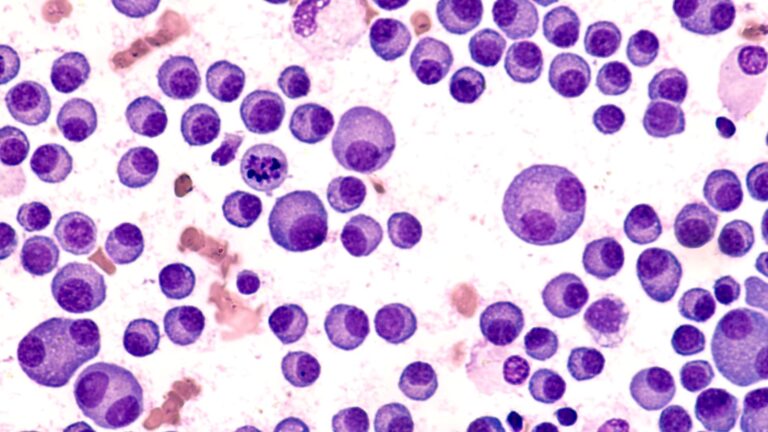

Galaktozemia (w klasyfikacji ICD-10 oznaczona kodem E74.21) to wrodzone zaburzenie metabolizmu galaktozy – cukru obecnego przede wszystkim w laktozie, czyli cukrze mlecznym. Organizm zdrowej osoby rozkłada galaktozę dzięki działaniu określonych enzymów. U pacjentów z galaktozemią brakuje jednego z nich lub jego aktywność jest znacznie obniżona.

W efekcie galaktoza i jej toksyczne metabolity odkładają się w tkankach, prowadząc do uszkodzeń wątroby, nerek, ośrodkowego układu nerwowego i soczewki oka.

Najczęstszą postacią jest klasyczna galaktozemia wynikająca z niedoboru enzymu GALT (galaktozo-1-fosforan urydylotransferazy). Istnieją też rzadsze warianty, jak niedobór enzymu GALK lub GALE.

- oznaczenie aktywności enzymu GALT,

- badanie stężenia galaktozo-1-fosforanu,